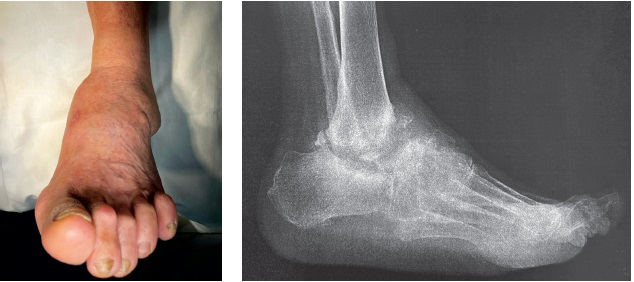

The patient underwent the described resectional tibiocalcaneal arthrodesis at the Foot Surgery Center of Yudin Hospital, with subsequent external fixation for seven months (Figure 3). After Ex-Fix removal, rehabilitation involved gradual weight-bearing in an immobilizing ankle brace with an air chamber for 10 months, followed by a transition to custom-made orthopedic footwear with a rocker bottom sole. The treatment outcome at 1.5 years is shown in Figure 4.

Figure 4. X-ray and photograph of the patient’s feet and ankle joints 1.5 years after dismantling the external fixation device